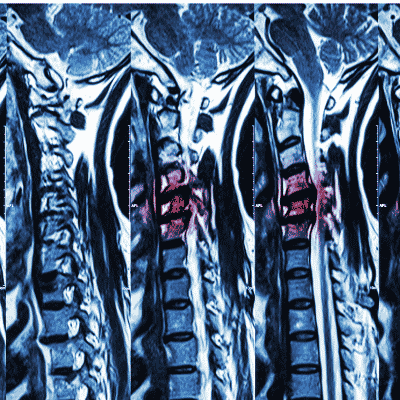

To learn about cervical disc replacement, it's best to know as much as possible about what a cervical disc is and what purpose it serves. Your cervical discs are cushions that lie between the seven [...]